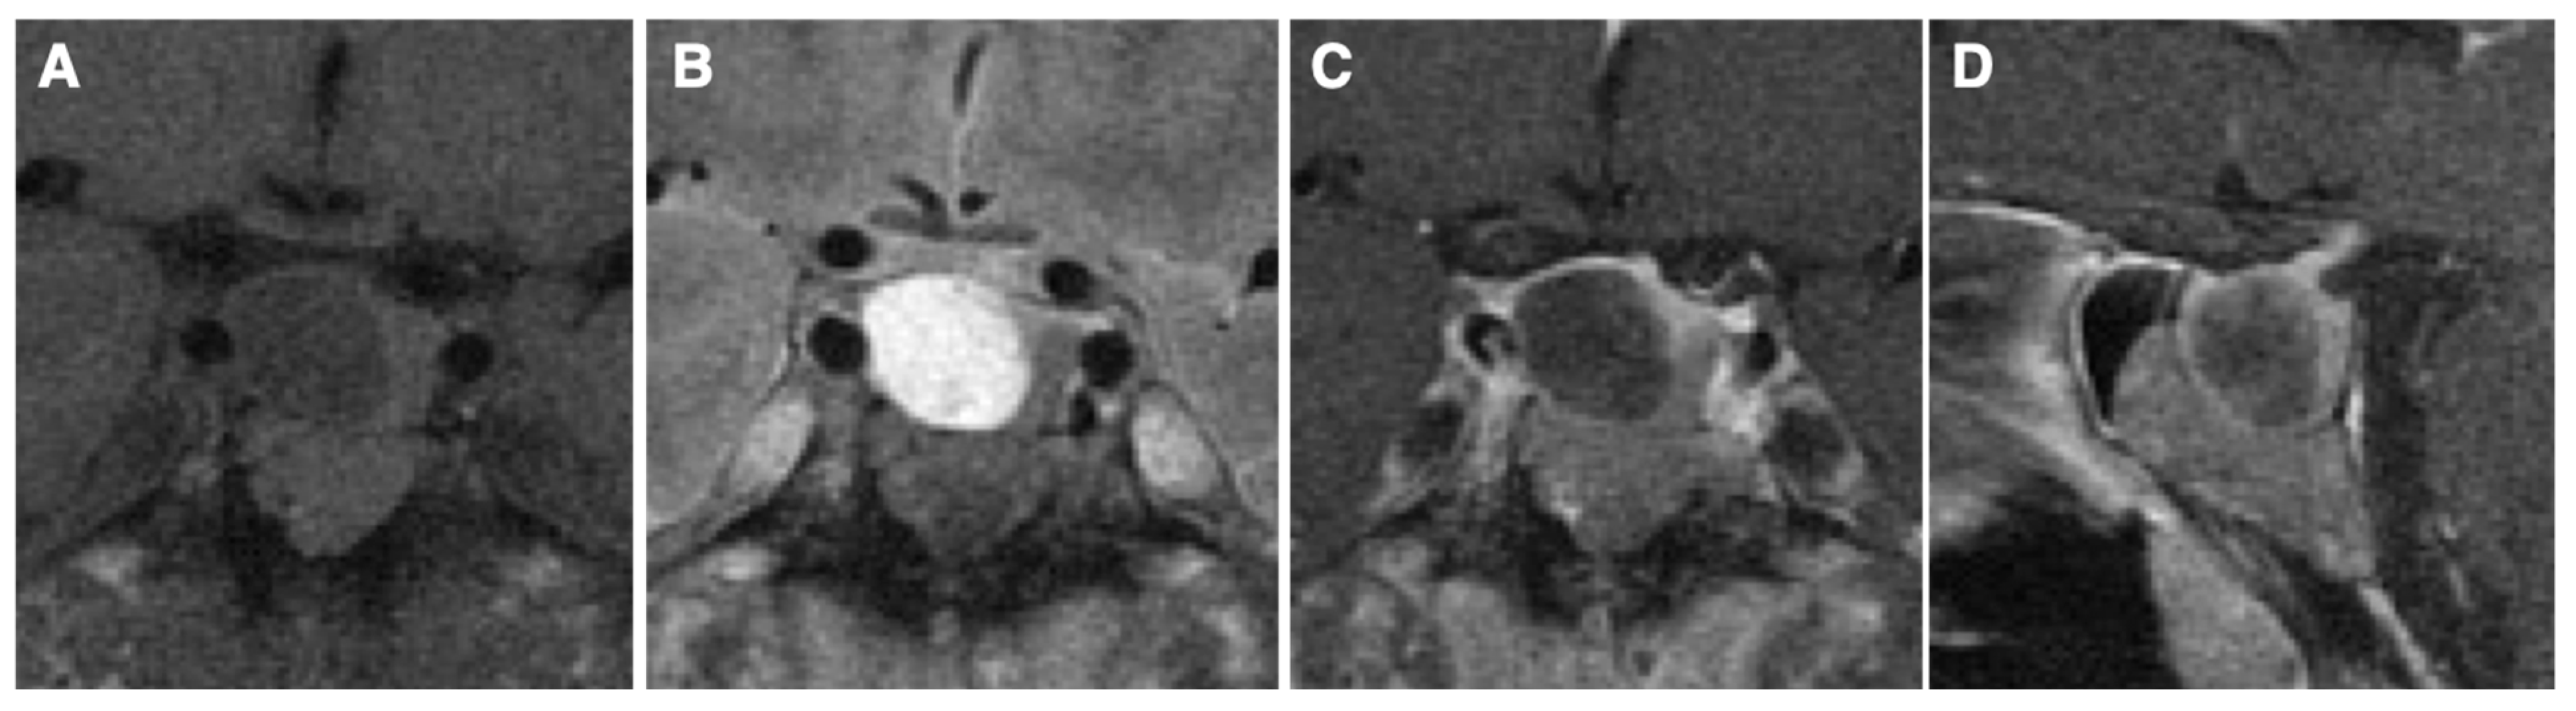

7. Clinical Phenotype

9. Radiological Findings